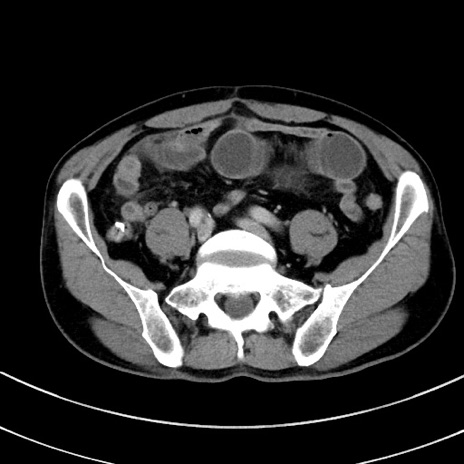

冠状断像

【症例】 60歳代男性

【主訴】 黒色吐物

【現病歴】 4日前から嘔気自覚、2日前の朝食後にも嘔気あり、自分で手で嘔吐反射起こし嘔吐したところ血が混ざっていたため受診。

【既往歴】 5年前汎発性腹膜炎を伴う急性虫垂炎で手術、高血圧、前立腺肥大症、高脂血症

【身体所見】 腹部正中に手術癩痕あり 腹部平坦・軟圧痛なし膨満感あり

【データ】WBC 8400、CRP 4.54